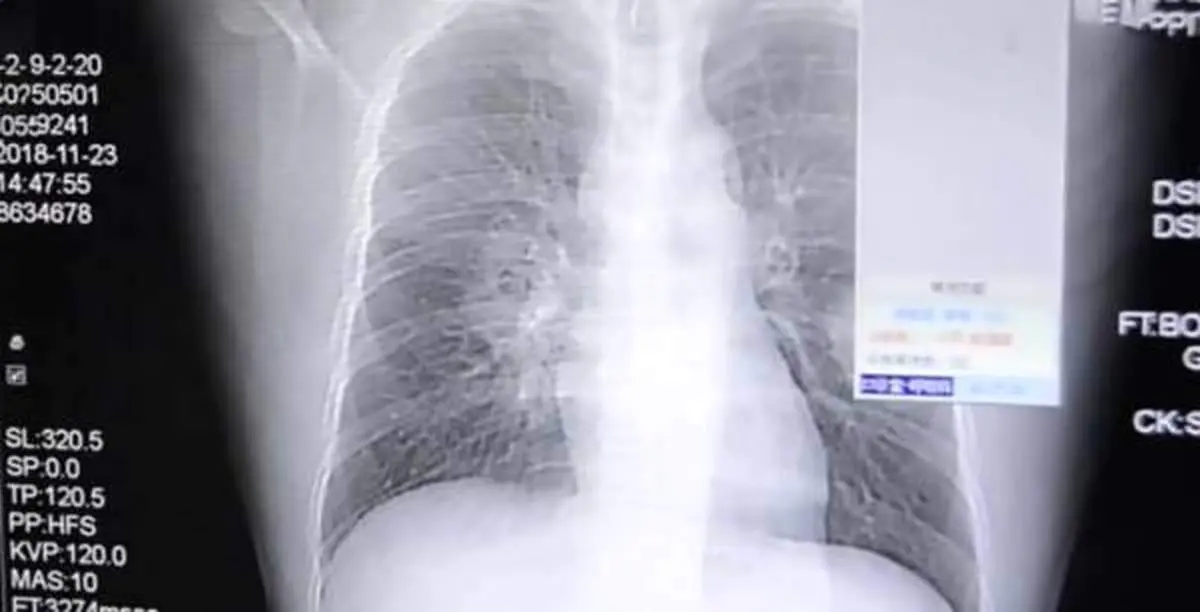

به گزارش منیبان؛ بوی جوراب !!! مگر می شود کسی تمایل به بو کردن جوراب هایش آن هم بعد از یک روز سخت کاری داشته باشد ؟ بله از قرار معلوم هستند افرادی که نه تنها جرات بو کردن جورابهایشان را دارند بلکه از این کار لذت می برند که این لذت به قیمت تهدید جانشان تمام می شود مثل مرد جوان چینی که با بو کردن جوراب های بد بوی خود راهی بیمارستان شد و بیماری جدی ریوی او بعد از عکسبرداری ها تشخیص داده شد.

این یک عادت عجیب و غریب مرد چینی 37 ساله است، او هر روز پس از بازگشت از کارش جوراب هایش را بو می کرد و این منجر به عفونت قارچی جدی در ریه هایش شد. او که تحت عنوان "پنگ" شناخته می شود، به علت سرفه های بدش و درد شدید قفسه سینه به بیمارستان ژانگژو در فوجیان رفت.